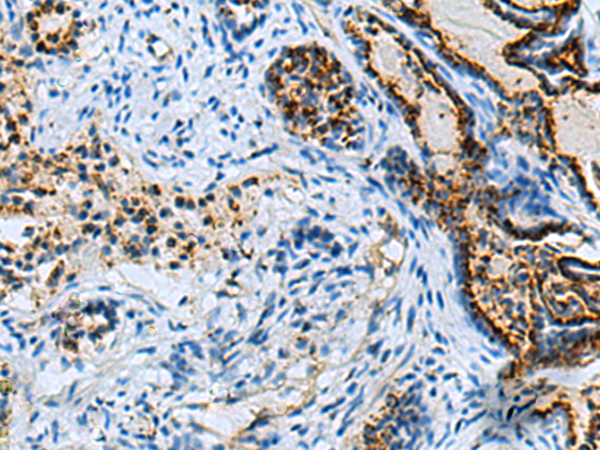

分类: 科研抗体货号: P06451别名: IL17; CTLA8; IL-17; CTLA-8; IL-17A应用: IHC反应种属: Human